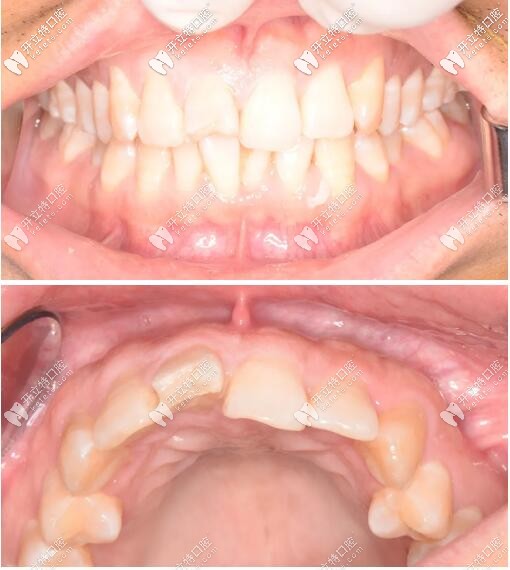

口內(nèi)檢查

被磕的11號(hào)牙(門牙)切端1/3折斷,并見不規(guī)則縱向裂紋;

牙齦色粉、質(zhì)韌,無(wú)明顯紅腫,牙齦乳頭充盈。